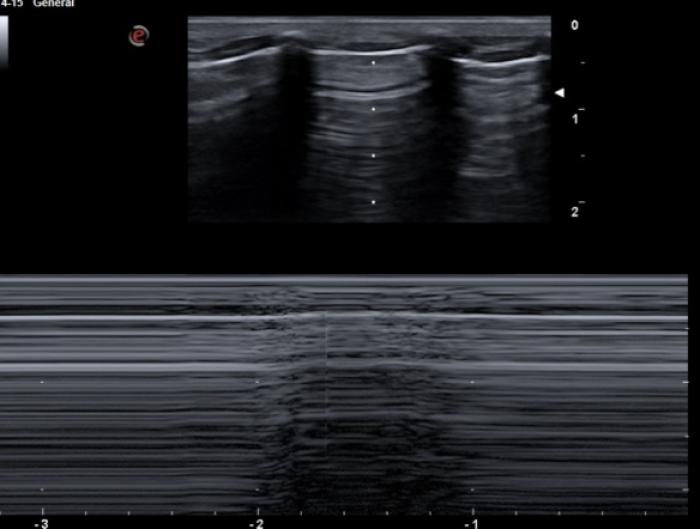

Líneas A

Son las líneas hiperecogénicas, horizontales, paralelas a la LP y equidistantes (su separación es la misma que existe entre la piel y la superficie pleural) que se van extendiendo hasta el fondo del campo ecográfico. Son fruto del reflejo del ultrasonido en el aire pulmonar, volviendo este a la sonda y creando la repetición de dicha superficie (reverberación).

Son visibles en todo pulmón bien ventilado, pero también estarán presentes en el neumotórax por lo que en este punto es vital observar el deslizamiento de la LP para su diferenciación (Figura 3A-B).